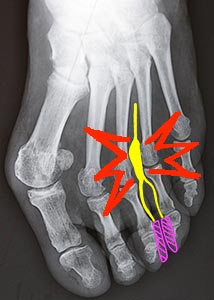

C'est le gonflement d'un nerf situé entre 3ème et 4ème métatarsiens (parfois entre 2 et 3ème), en réaction à une compression.

Le nerf (en jaune) est pincé dans un espace naturellement étroit, encore rétréci par le gonflement des articulations voisines si elles sont surmenées.

Quand le syndrome est typique, les douleurs siègent à l'avant du pied, entre 3 et 4ème orteils, elles augmentent quand on resserre le pied (chaussure étroite) et obligent à se déchausser.

Les crises douloureuses, souvent très aigües, s'accompagnent d'un manque de sensibilité sur les côtés des orteils correspondants (en mauve).

Si les douleurs persistent, l'opération est conseillée. Elle consiste à enlever le névrome, ce qui entraine une disparition de la sensibilité dans la petite zone correspondante (en mauve), causant une gêne minime.